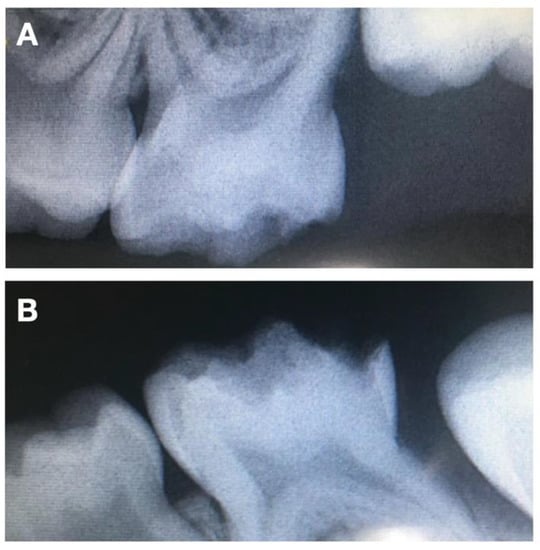

Considering her young age, her non-cooperative behavior, the fact that the severity of the HPSM, which includes teeth 65 and 75, had big proximity to the pulp (Figure 2), and the importance of the second primary molars, it was advised to place four crowns on all second primary molars. Two treatment options were presented to the patient’s parents. The first was four zirconia crowns on the four primary molars. However, this was rejected duo to the high economic value, despite the aesthetics, the mechanical resistance, limited plaque adhesion, wear behavior and natural appearance. The second treatment option was four stainless steel crowns. This last option allows the eruption of the first definitive molars, maintains the vertical dimension, and grants the physiological exfoliation of the primary second molars at a lower cost. Firstly, nitrous oxide sedation was proposed, but it was not successful, given the non-cooperative behavior. Therefore, the complete treatment was performed under general anesthesia. After plaque removal with a prophylactic paste at the beginning of the procedure and the gently drying of the tooth, a rubber dam was applied, one tooth at a time, to locally isolate the lesions. Then, and after partial carious lesion removal, stainless steel crowns (3M™ ESPE™ Stainless Steel Crowns, 3 M, St. Paul, MN, USA) were selected and cemented with Ketac™ Cem Easy Mix (3M™ ESPE™, Maplewood, MN, USA), according to the manufacturer’s instructions (Figure 3). Excess cement was removed. The position of the margins was sub-gingival, and both sides of each tooth had contact with adjacent teeth to allow proper oral hygiene.

Figure 2. Pretreatment radiographs illustrating preoperative (A) periapical X-ray of 65 and (B) periapical X-ray of 75.